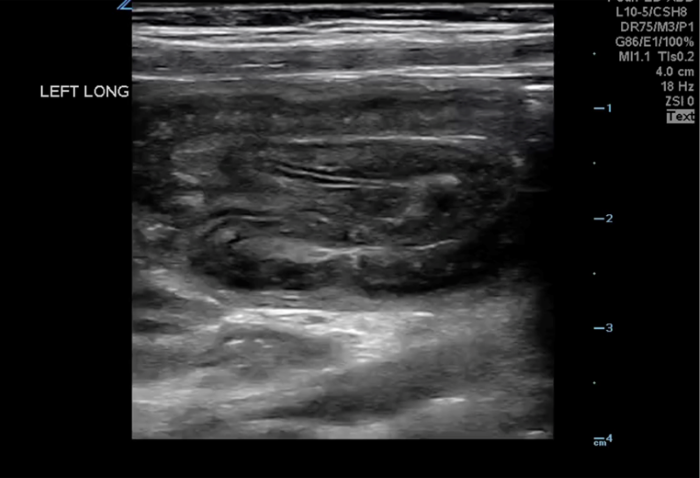

The abnormal structure of intussusception is a rounded tissue mass in the transverse axis with a hyperechoic center and hypoechoic outer muscle layer (Figure 5) and in long axis appears as a “pseudokidney.” (Figure 6) Outer dark edge to edge should be at least 2cm.1-3 Smaller structures with similar appearance are likely ileo-ileal intussusception, which is usually psychologic and does not typically require intervention.

10-2024 Article7-6.pngFigure 6. Long axis Intussusception, sometimes referred to as the “Pseudokidney” as it mimics the kidney’s shape in sagittal.